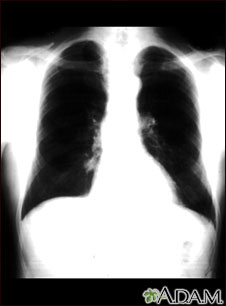

Nódulo pulmonar - Vista frontal de la radiografía de tórax

Ésta es una radiografía del tórax que muestra una masa en la parte inferior del pulmón derecho, cerca al corazón (se puede observar del lado izquierdo de la imagen).